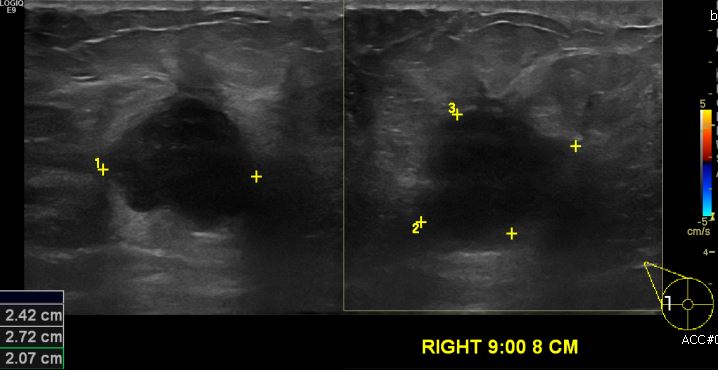

상기환자 우측유방에 만져지는 멍울과 통증으로 내원하신 60대 여성분으로 우측

9시 방향에서 8cm 떨어진 거리의 멍울 조직검사 시행하여 우측 침윤성유관암 진단

되었습니다.